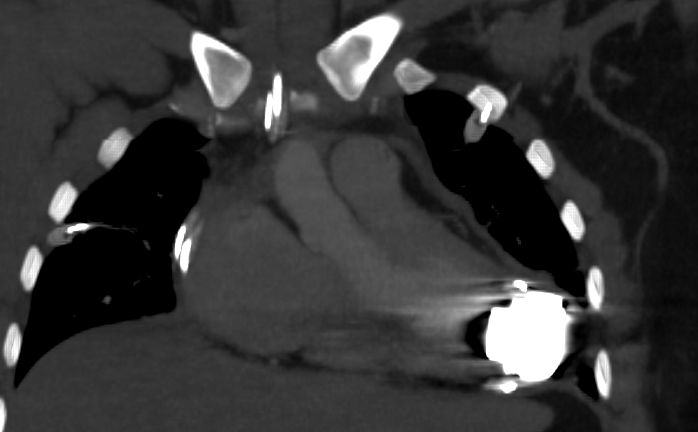

Types de LVAD

Heartmate II

Heartmate III

Heartmate XVE

Jarvik 2000

VentrAssist

Retrait de LVAD (pas de vis résiduel)